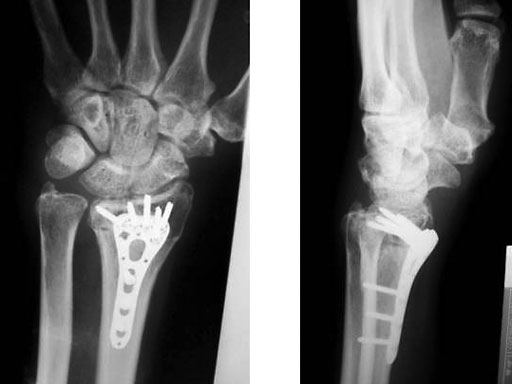

Fig 3ac Postoperative x-rays showing comparison of plate alternatives.

Fig 2a-b Post-op immediate

Fig 3a-b Post-op 3 months